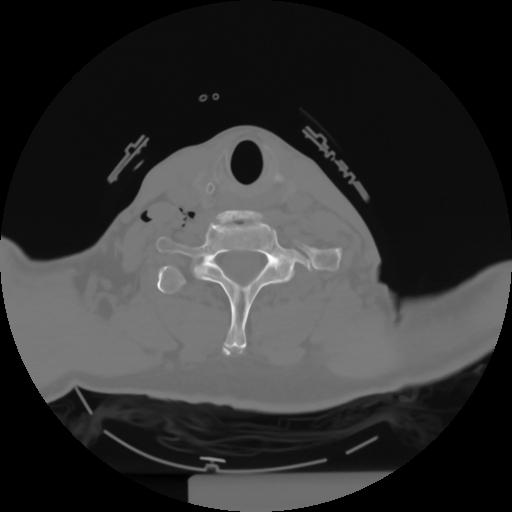

10 P.BLANDAS,,Axial,2.0,P.BLANDAS,,